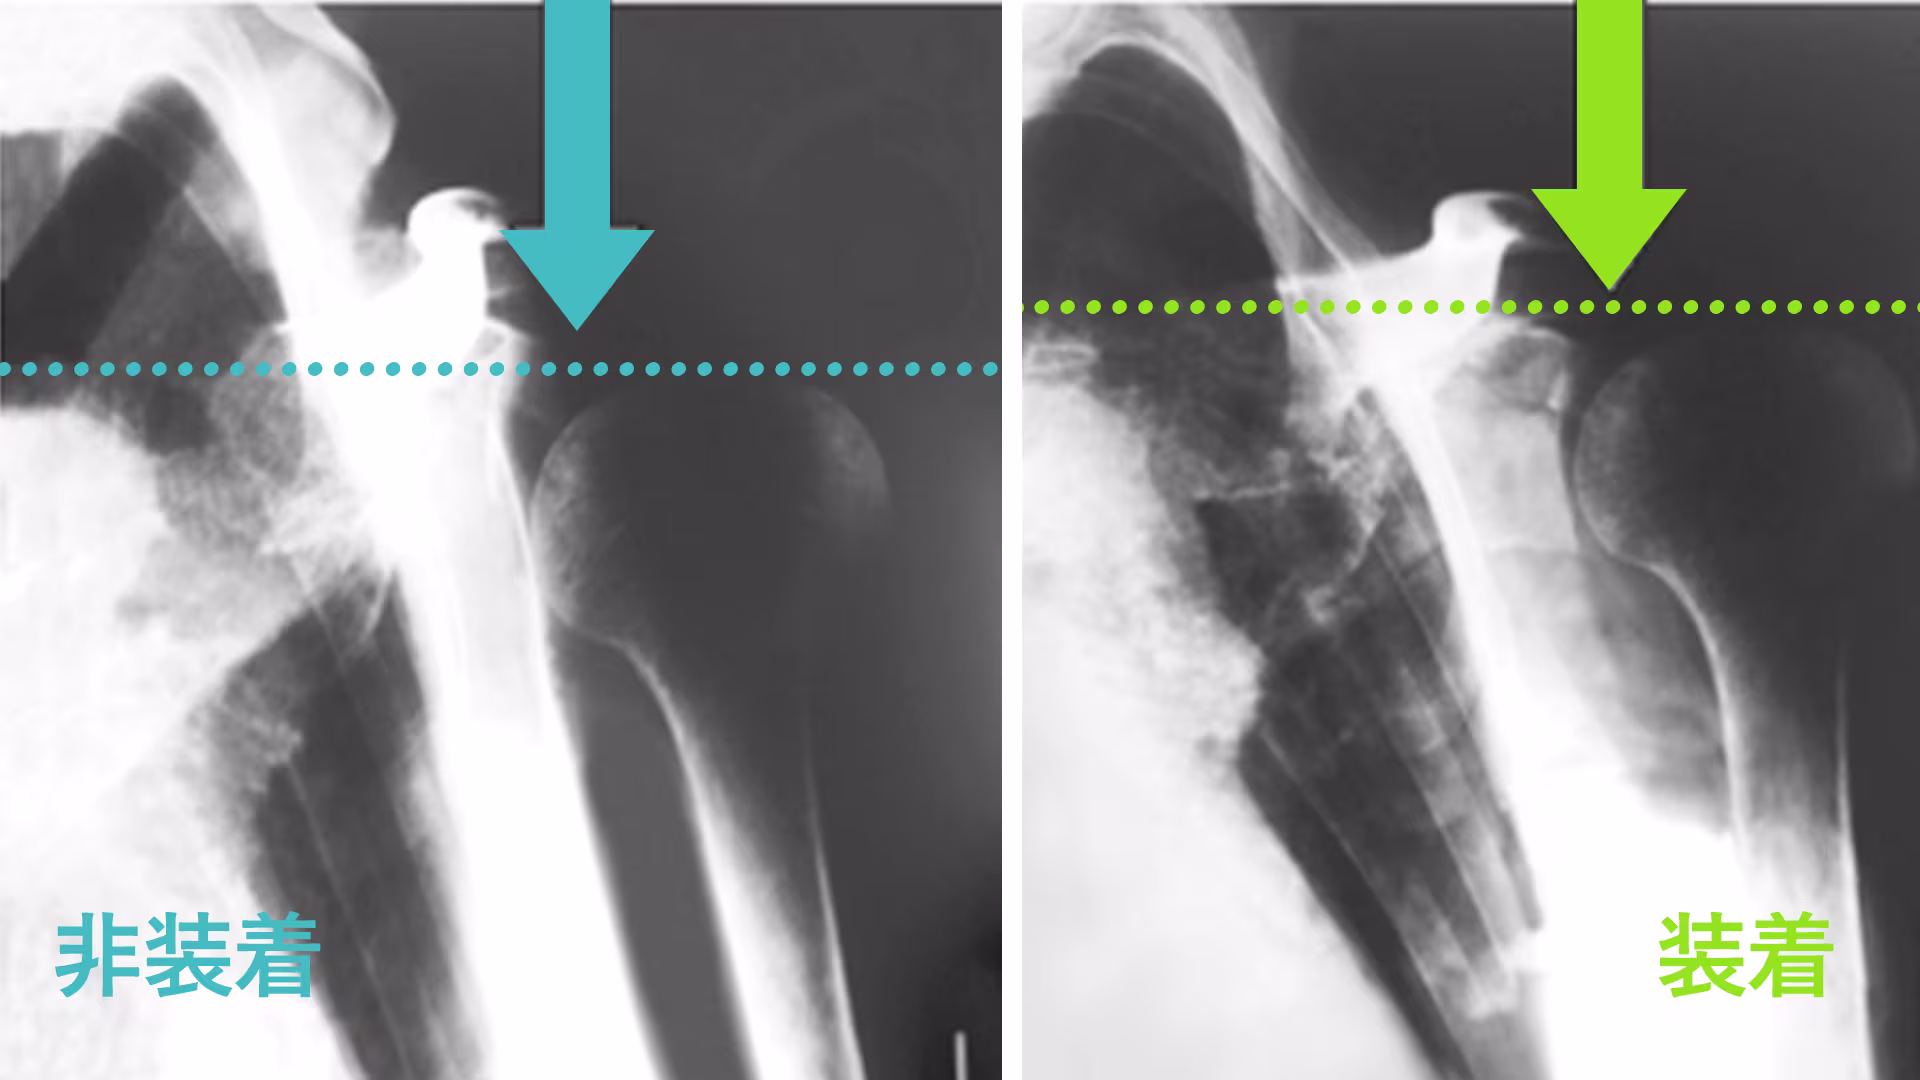

肩関節(上腕骨頭)の位置改善

写真は肩関節亜脱臼に対し、オモニューレクサ プラスの非装着時(左)と装着時(右)の上腕骨頭の位置をレントゲンで撮影したものです。オモニューレクサ プラスを装着することで、上腕骨頭の位置が改善された様子が確認できます。